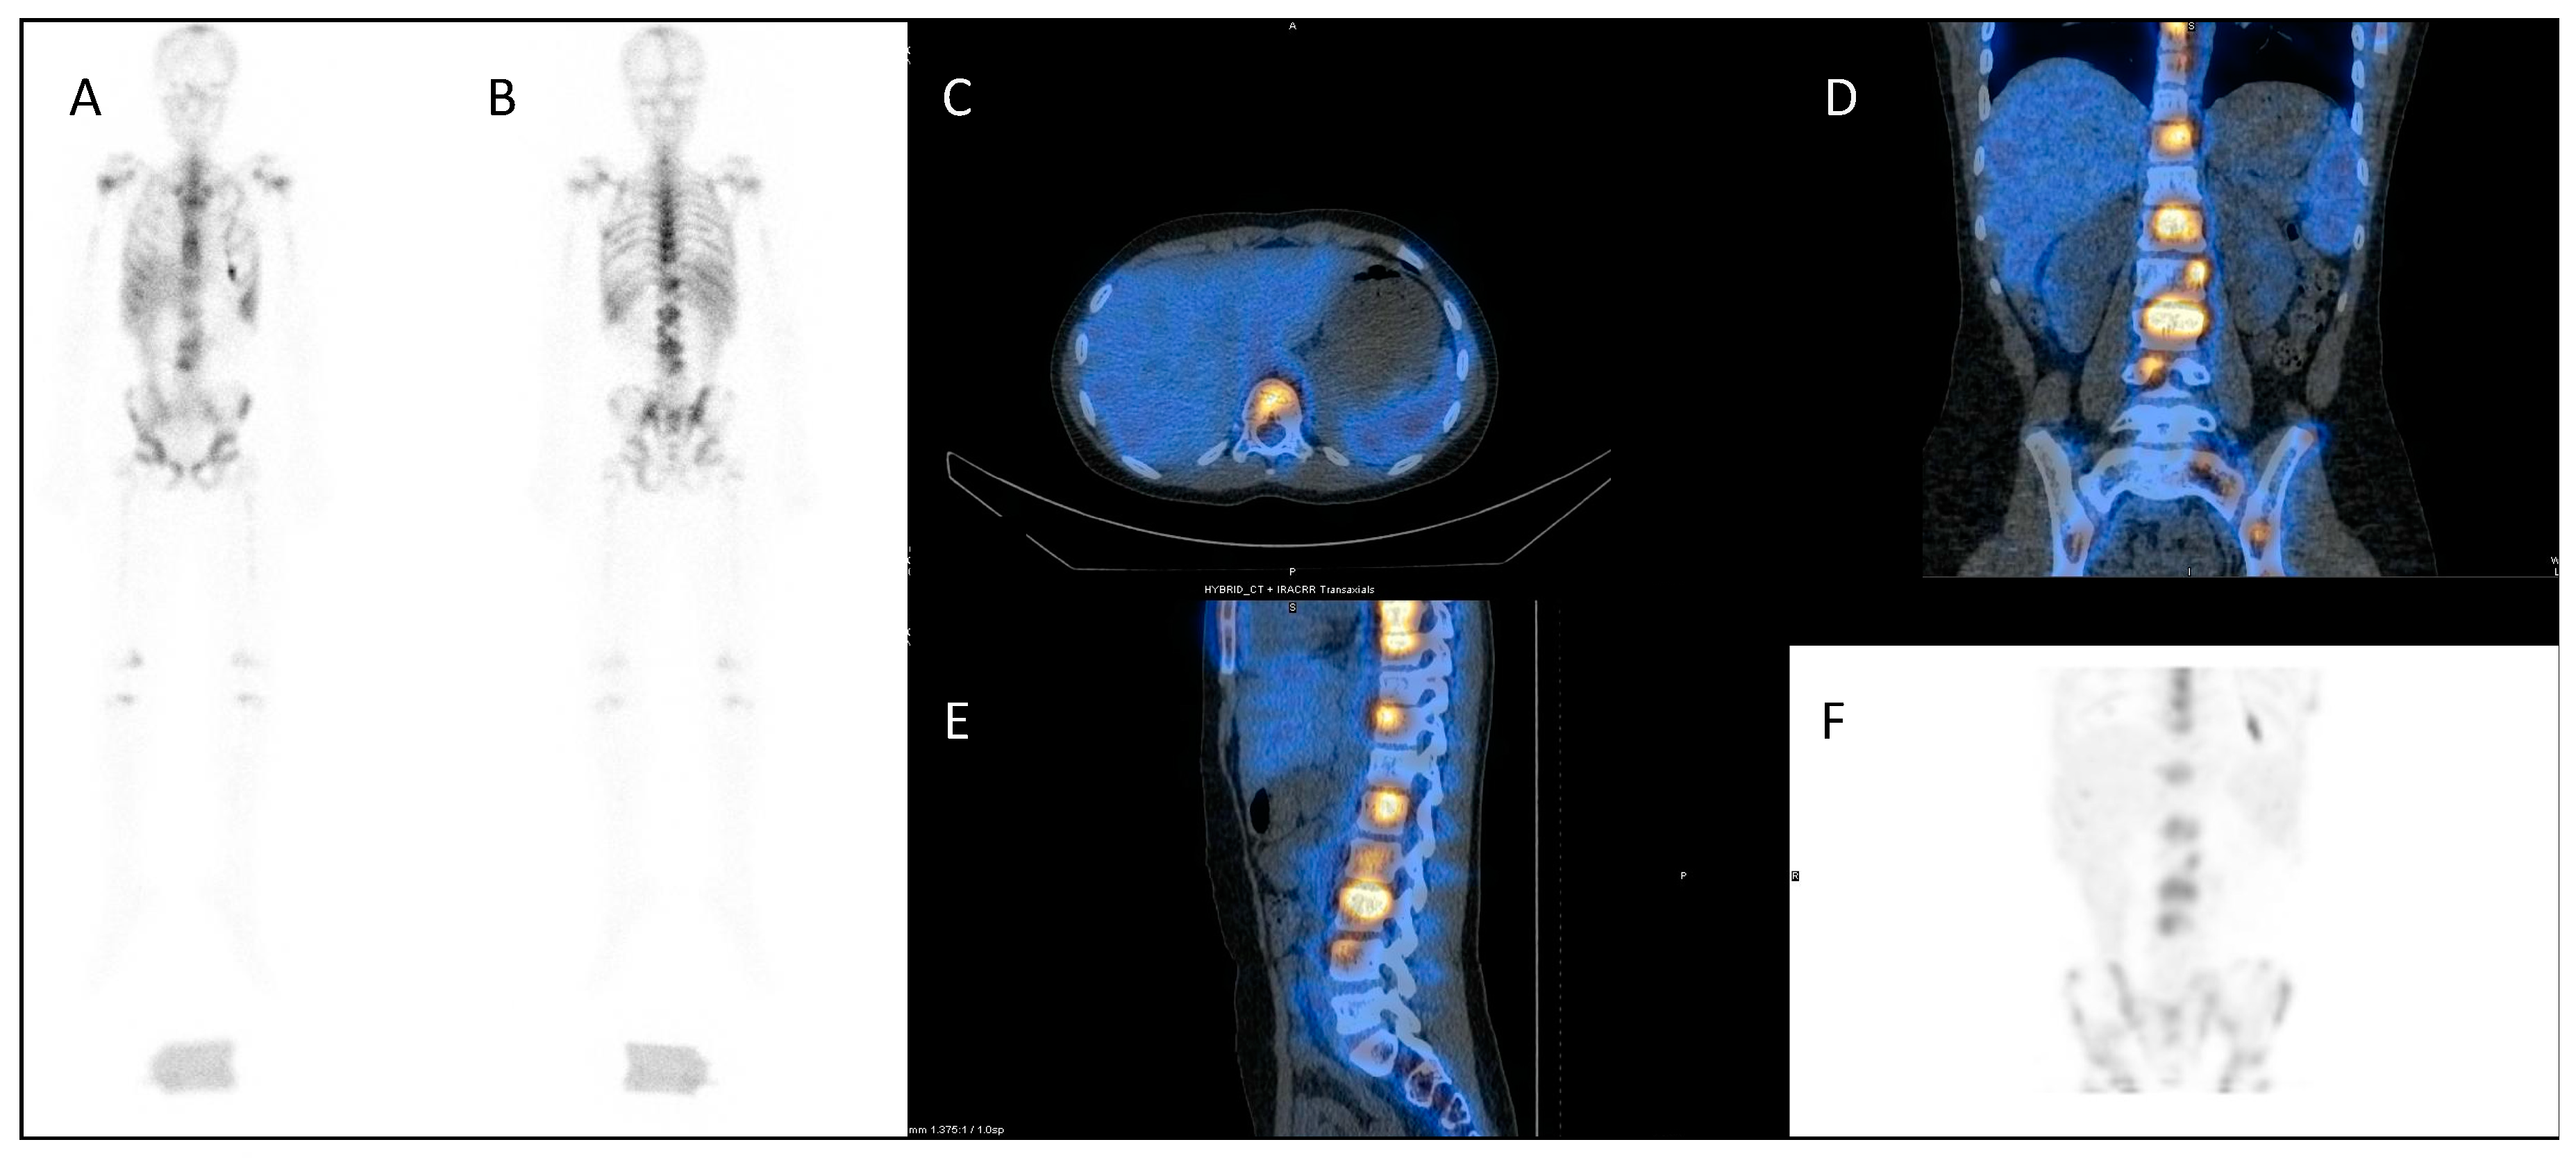

123I mIBG (meta-Iodobenzylguanidine) scintigraphy is the gold standard imaging modality for staging in neuroblastoma (Figure 1A,B), and various semi-quantitative systems have been devised which correlate with prognosis [15,16,17]. Over 90% of patients with neuroblastoma express the noradrenaline transporter molecule and so take up mIBG [18], and scintigraphic demonstration of this is used to select patients for 131I mIBG therapy (Figure 1C,D) [19].

Figure 1.

An example of a theragnostic pairing of radiopharmaceuticals in a child with metastatic neuroblastoma. Diagnostic 123I-mIBG imaging (A) anterior and (B) posterior views of whole-body planar scintigraphy demonstrating pathological uptake in a large left sided retroperitoneal mass as well as in metastatic disease in the femora and jaw, as well as physiological uptake in the salivary glands, heart, liver, urinary bladder and (despite blockade) in the thyroid gland. Corresponding (C) anterior and (D) posterior images following 131I-mIBG therapy administration showing uptake of the agent in the tumour and metastases as well as in physiological sites.